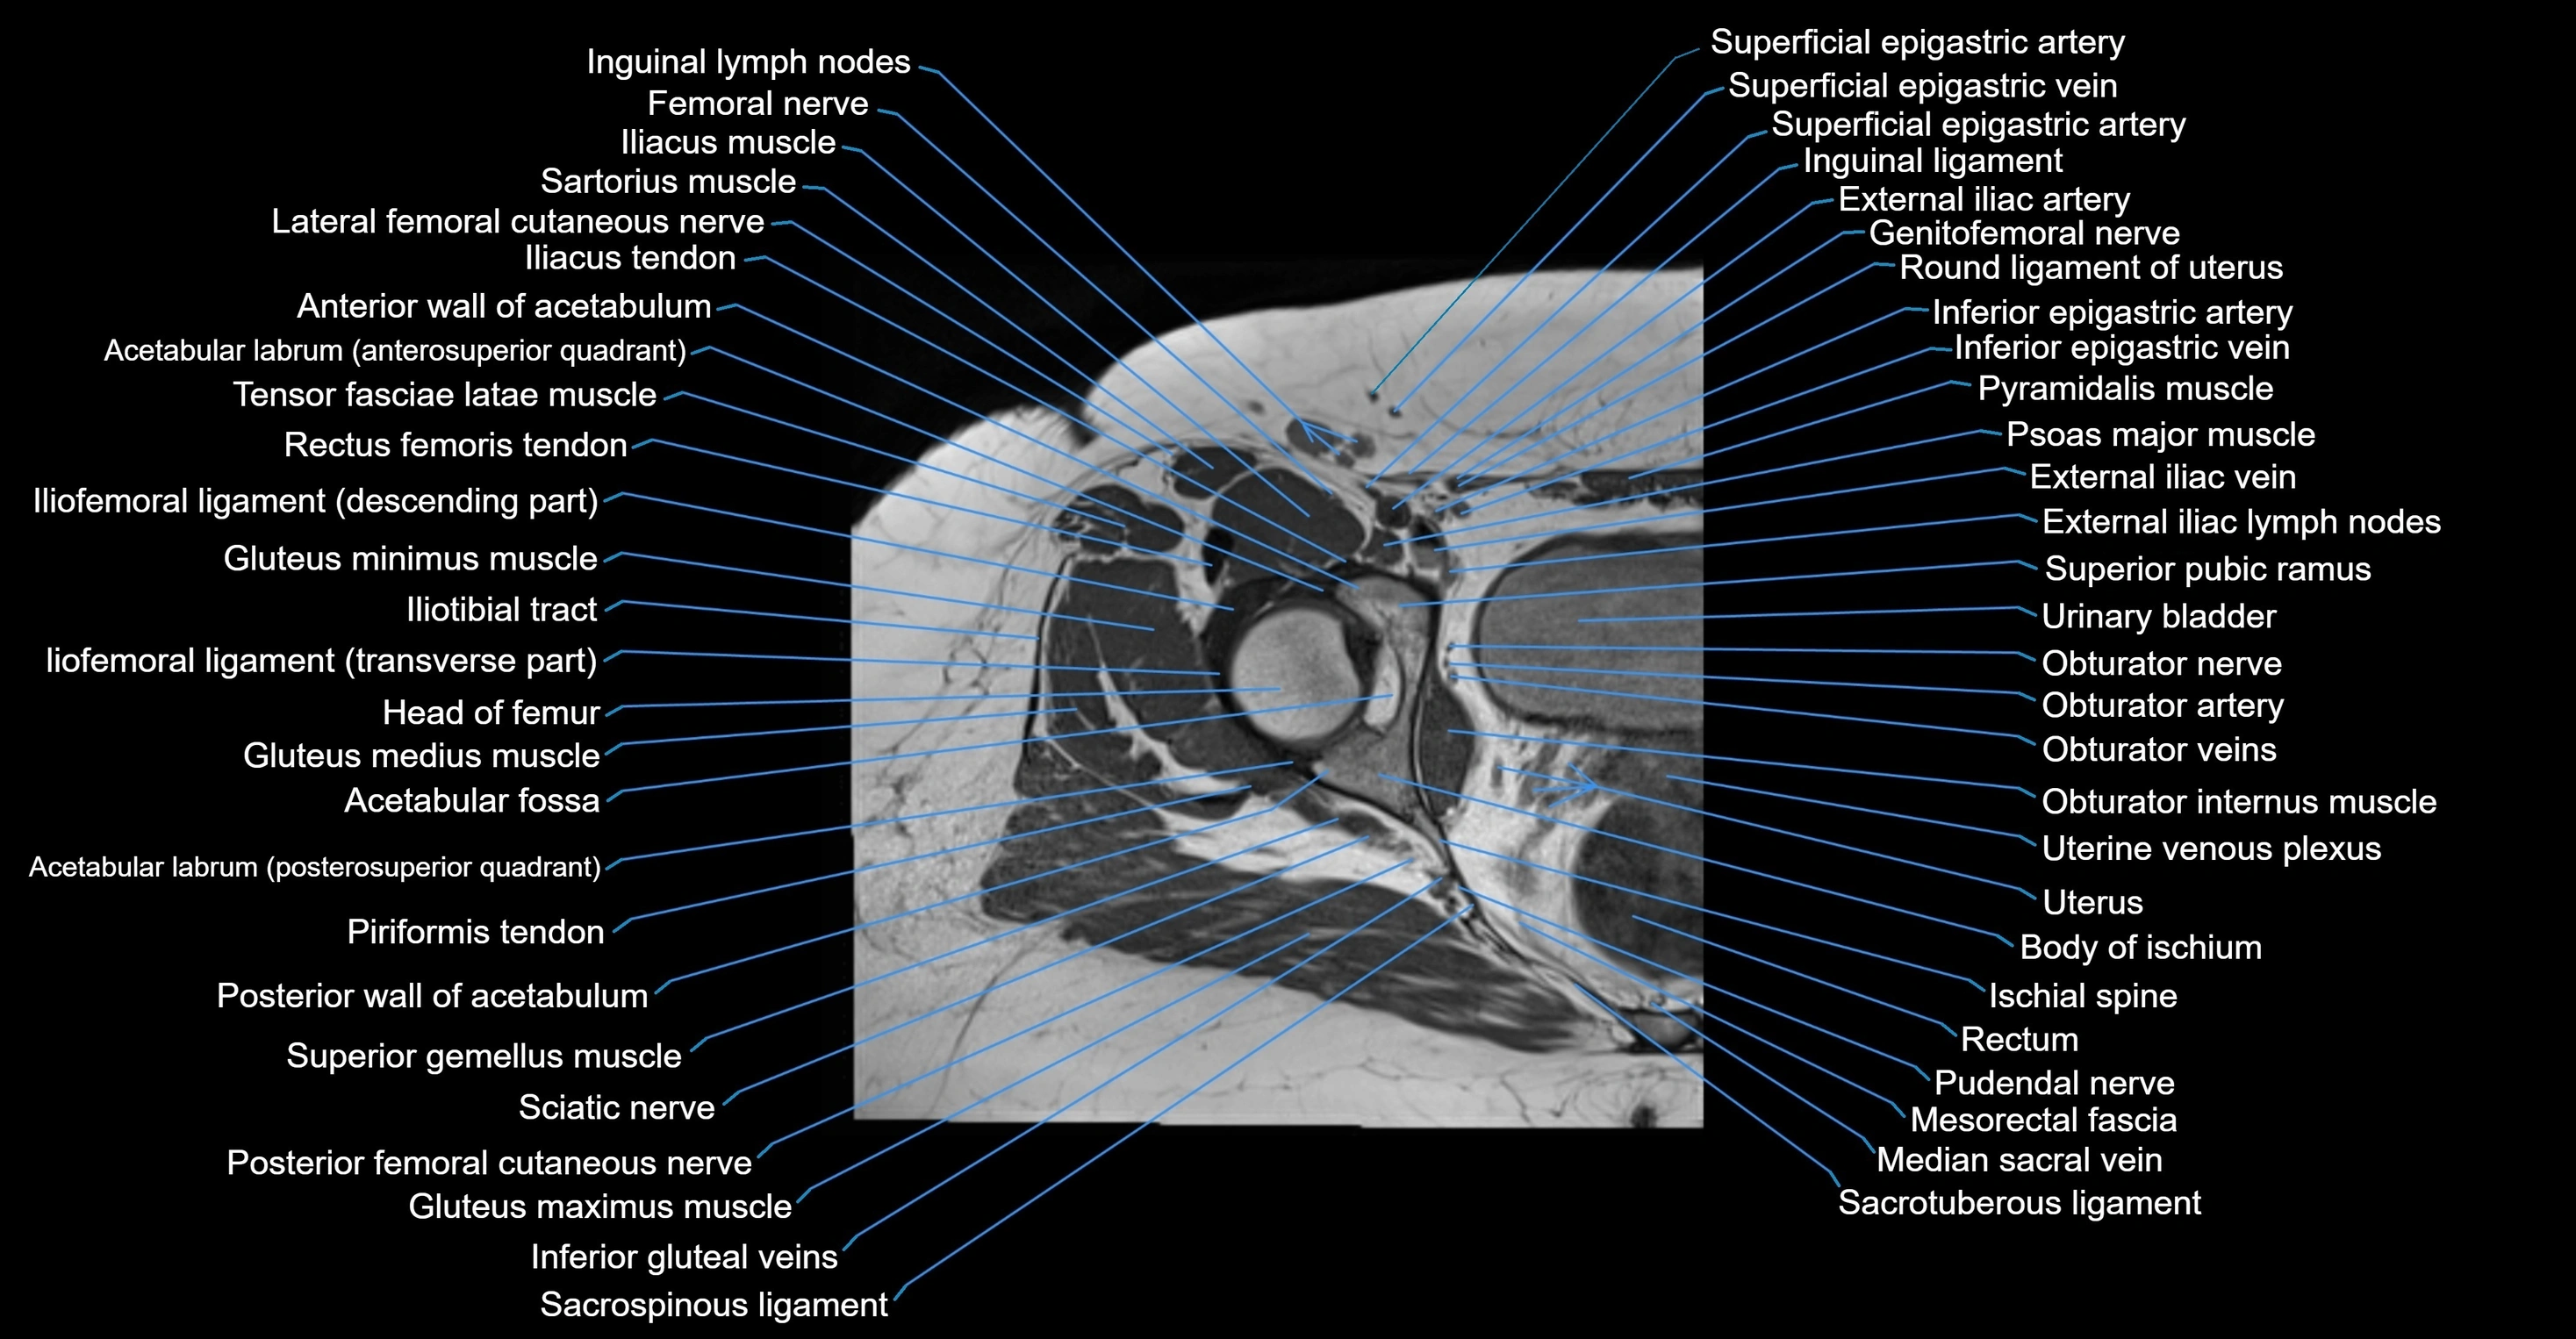

- Acetabulum

- External iliac artery

- External iliac vein

- Femoral nerve

- Genitofemoral nerve

- Gluteus maximus muscle

- Gluteus medius muscle

- Gluteus minimus muscle

- Head of femur

- Iliopsoas muscle

- Iliotibial tract

- Inguinal lymph nodes

- Ischial spine

- Ligamentum teres (ligament of the head of femur)

- Mesorectal fascia

- Obturator internus muscle

- Obturator internus tendon

- Obturator nerve

- Obturator veins

- Pudendal nerve

- Rectum

- Sacrospinous ligament

- Sacrotuberous ligament

- Superior gemellus muscle

- Tensor fasciae latae muscle

- Urinary bladder

- Uterus